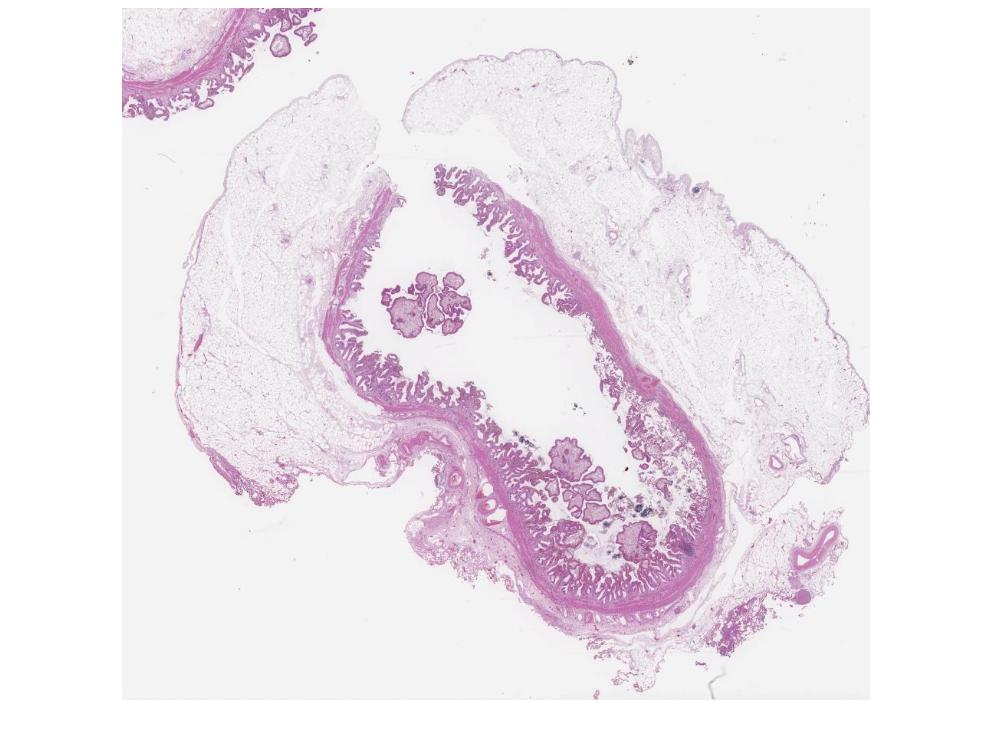

2.1 Kolesterol Polibi

Mikroskopik görüntüleri inceleyin: